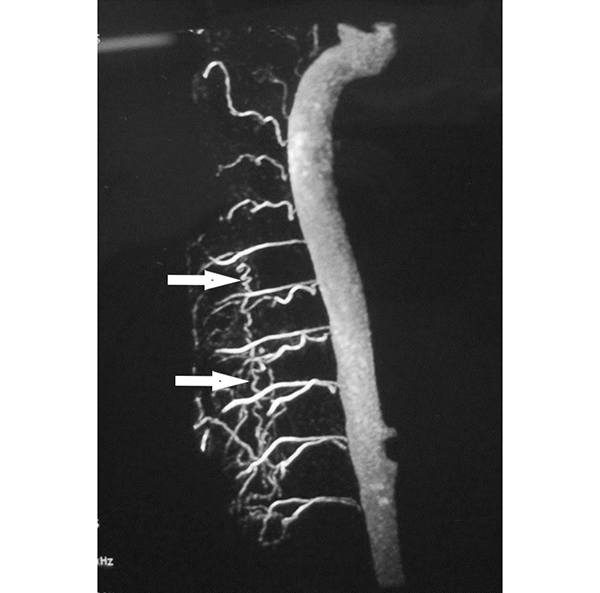

Figura 4: Caso #1. ARM de alto campo en tiempo arterial que muestra a la arteria Aorta con sus vasos segmentarios y la presencia de una vena serpiginosa longitudinal (flechas blancas).

CASO #1. Paciente masculino de 52 años con una historia de 6 meses de evolución de disestesias en ambos miembros inferiores, inestabilidad en la marcha, hiperreflexia y urgencia miccional. Se estudió con RMN (Fig. 3), ARM (Fig. 4) y ADM seguida de embolización con oclusión total de una FDAVE D8 izq. (Fig. 5). Evolucionó sin déficit y a los 11 meses comenzó con la misma sintomatología previa a la embolización. Se estudió nuevamente y la ADM (Fig. 6) mostraba la recidiva de la FDAVE y fue derivada para microcirugía (Fig. 7). Luego de la cirugía evolucionó sin déficit, se realizó una ADM diferida (Fig. 8) y lleva 116 meses libres de enfermedad.